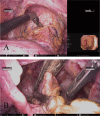

Background: The hinotori™ Surgical Robot System was approved for use in colorectal cancer surgery in Japan in 2022. This robot has advantages, such as an operation arm with eight axes, an adjustable arm base, and a flexible three-dimensional viewer, and is expected to be utilized in rectal cancer surgery. Herein, we report the world's first surgery for rectal cancer using the hinotori™ Surgical Robot System.

Case presentation: A 71-year-old woman presented to our hospital with bloody stools. A colonoscopy revealed type 2 advanced cancer in the rectum, and a histological examination exposed a well-differentiated adenocarcinoma. Abdominal enhanced computed tomography divulged rectal wall thickening without significant swelling of the lymph nodes or distant metastasis. Pelvic magnetic resonance imaging showed tumor invasion beyond the intrinsic rectal muscle layer. The patient was diagnosed with cStage IIa (cT3N0M0) rectal cancer and underwent low anterior resection using the hinotori™ Surgical Robot System. Based on an adequate simulation, surgery was safely performed with appropriate port placement and arm base-angle adjustment. The operating time was 262 min, with a cockpit time of 134 min. Subsequently, the patient was discharged 10 days postoperatively without complications. The pathological diagnosis was pStage IIA (cT3N0M0) and the circumferential resection margin was 6 mm.